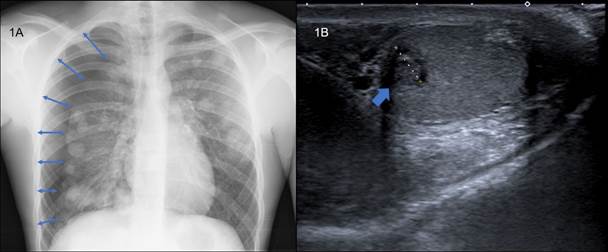

Se realizó analítica básica: el hemograma mostraba leucocitosis de 13 900 con neutrofilia y sin anemia. La glucosa era de 219 mg/dl con iones y función renal normales. La PCR era de16 mg/l. En la radiografía de tórax se apreciaba un neumotórax derecho de un 40 % y una imagen en suelta de globos en ambos campos pulmonares (Figura 1A). Se colocó un tubo de drenaje endotorácico. Dado el hallazgo radiológico, realizamos exploración de genitales sin objetivar ninguna alteración; sin embargo, dadas las características del caso, se solicitó una beta-HCG urgente, obteniéndose un valor de 89 900 mUI/ml. Se realizó una ecografía testicular donde apreciamos una lesión pseudonodular en el testículo izquierdo de 8 x 9 mm con presencia de microcalcificaciones y vascularización intratesticular sugestivo de proceso neoformativo primario (Figura 1B). Se decidió ingreso hospitalario para ampliación de estudio.